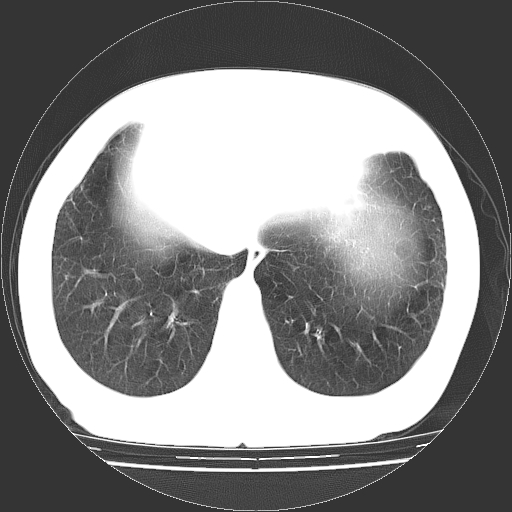

标题: CT13141:女,70岁,咳嗽、胸闷半个月。 [打印本页]

标题: CT13141:女,70岁,咳嗽、胸闷半个月。

女,70岁,咳嗽、胸闷半个月。纵隔窗未见异常,未上传。

双肺肺气肿并多发肺大泡

慢性支气管炎合并小叶中心性肺气肿,多发性肺大泡

慢性支气管炎并小叶中心性肺气肿及间隔旁肺气肿.(多与吸烟有关)。

多发肺大泡

小叶中心型肺气肿